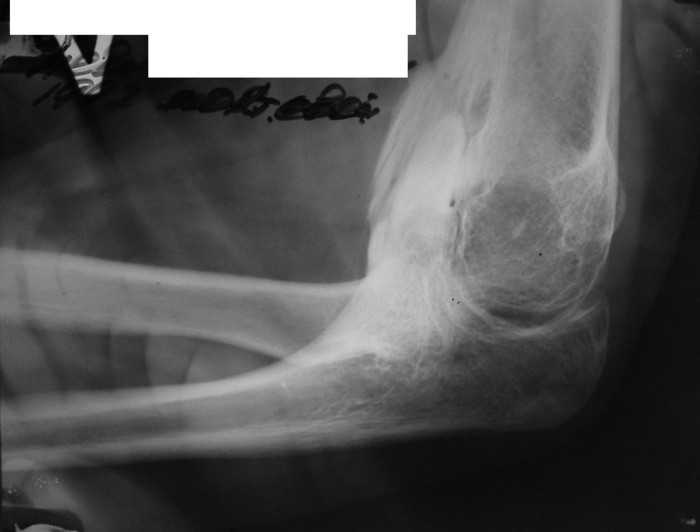

Жалобы: на нарушение функции верхних конечностей: невозможность движения в обеих правых плечевых и локтевых суставах; ограничение движений в шейном отделе позвоночника, наличие опухолевидных множественных образований на спине и пробам бедре.

Анамнез заболевания: со слов матери появлению множественных опухолевидных образований на спине предшествовал массаж воротниковой зоны в 4 года. Консультирован в Областной детской больнице и Областном онкодиспансере. В декабре 2010 г. после падения с велосипеда ушиб левый локтевой сустав, a в январе вторичное падение с велосипеда с ушибом правого локтевого сустава, после чего пациент отметил постепенное ухудшение функции обеих верхних конечностей вплоть до резкого ограничения объема движений в обеих плечевых и локтевых суставах.

Место болезни: при осмотре определяется - вынужденное положение верхних конечностей в плечевых и локтевых суставах, множественные опухолеподобные образования вдоль позвоночника и по наружной поверхности верхней трети левой бедренной кости округлой формы, с четкими контурами, неподвижные, безболезненные, каменистой плотности. приводяще-отводящая контрактура в обеих плечевых суставах, сгибательно-разгибательная контрактура в обеих локтевых суставах с сохранение про- и супинационных движений. Объем движений в пальцах кисти и лучезапястных суставах в полном объеме без ограничений, безболезненный.

Диагноз: врожденная аномалия развития шейного отдела позвоночника с резким нарушением функции в плечевых и локтевых суставах, множественных костно-хрящевые экзостозы, оссифицирующий миозит.

рентгенограммы

это fibrodysplasia ossificans progressiva, генетически обусловленная прогрессирующая метаплазия соединительной и мышечной ткани в костную. Лечится (вернее, тормозится) консервативно, после попыток оперативного лечения и после травм - прогрессирует.